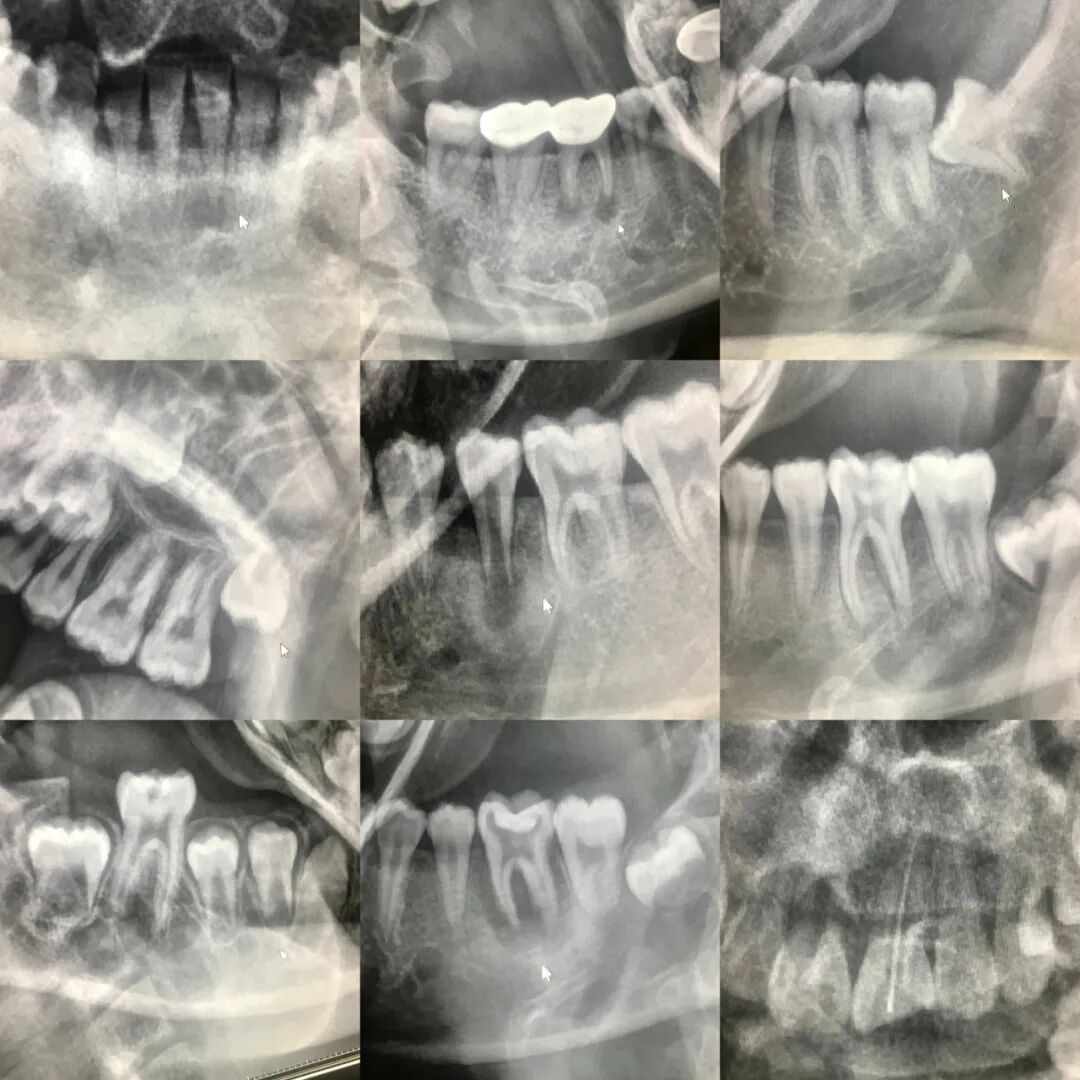

我们来看一组对比图

口腔ct怎么拍摄口腔全景CT落户阳山镇卫生院,看牙更精准、更高效_https://www.jmylbn.com_新闻资讯_第3张上图是我院放射科用DR机拍出的牙片。